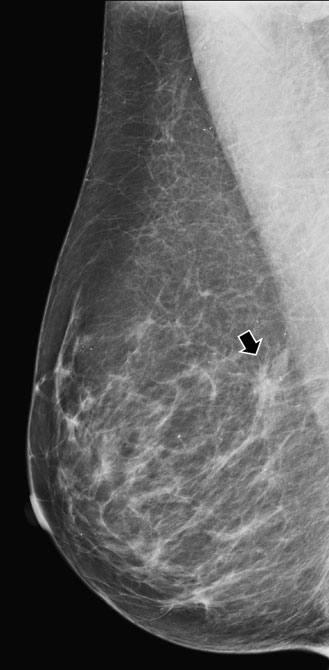

superimposed tissue

A mammogram (above) showing possible asymmetry, with tomosynthesis images (right) showing superimposed tissue.